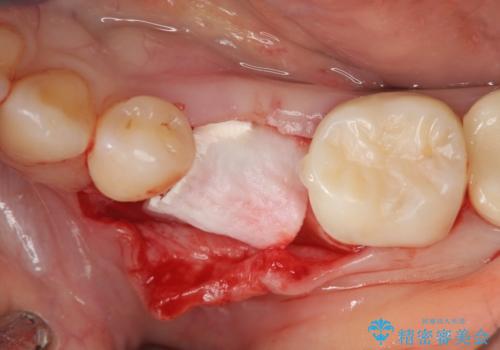

- 残していた乳歯がぐらつき始め、抜去ののちのインプラント治療を希望され来院されました。

乳歯を抜去して歯ぐきの状態が落ち着いたのち、骨の増成を伴うインプラント治療を行い機能の回復を図ります。